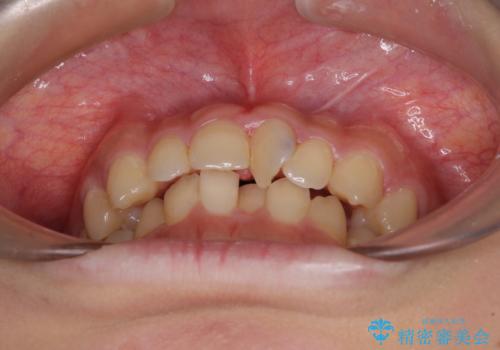

- 前歯のデコボコと深い咬み合わせを改善したいとのことで来院された患者様です。

奥歯の咬み合わせは上顎に対して下顎が後方位にあり、上顎前歯で下顎前歯が隠れるような典型的な過蓋咬合です。

補助装置を用いて上顎大臼歯を後方に移動させながら、ワイヤー装置で歯列を整えて深い咬み合わせを挙上することとしました。